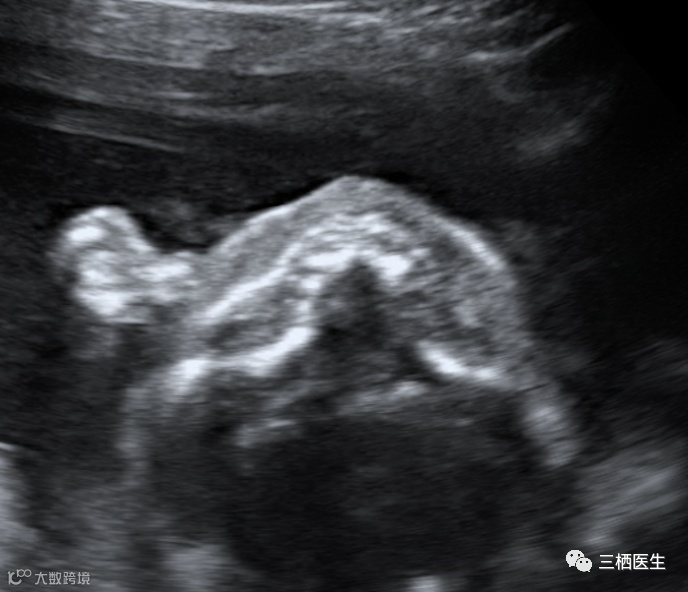

正常 (呈“等号”)

异常(呈“双等号”)

2.软腭线(如果软腭是好的,前面的硬腭也是好的)

完整的软腭线